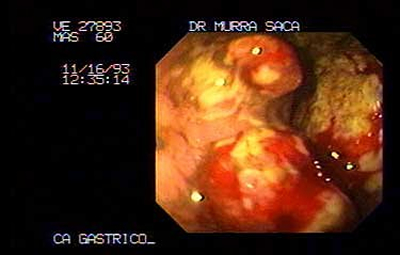

Imagen Endoscópica de extenso carcinoma obstructivo masculino 60 años:

-

Imagen endoscópica del mismo paciente descrito anteriormente con extenso carcinoma de cuerpo y antro.